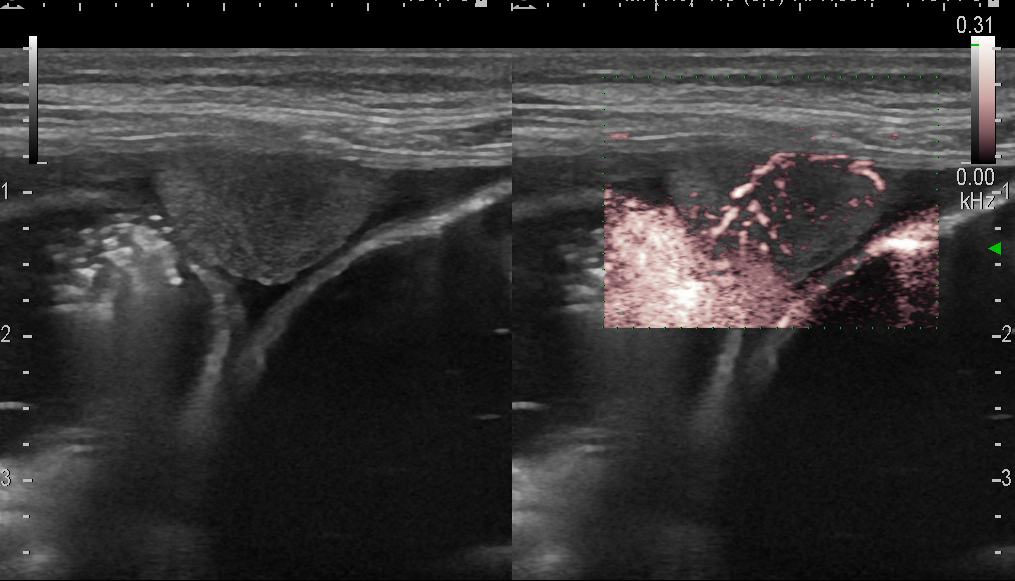

Канцероматоз брюшины у больной с опухолью толстой кишки

Линейный датчик 7-11 МГц.